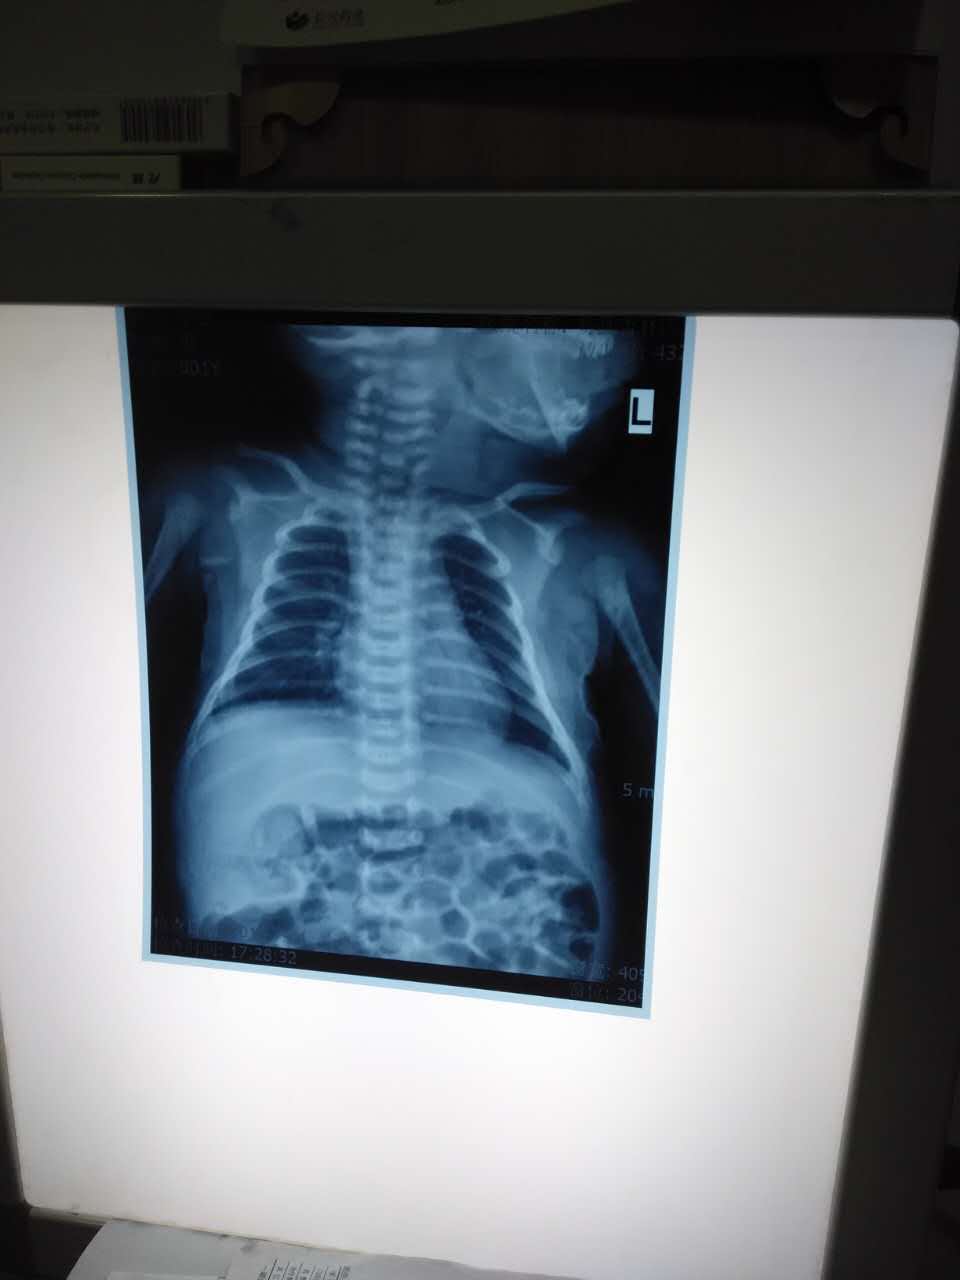

在我们采访即将结束的时候,发现小平安有些不舒服,甚至哭闹不止,我们便把小平安送到了杏林医院,经过血常规、胸部CT等初步常规检查,医生发现小平安腹部有大量气泡,并伴有轻微贫血,医生建议留院观察一晚,明天继续检查,重点检查项目为头部CT。在我们离开医院前,医务人员已经为小平安、李淑丽大姐及李艳大姐(前几日小平安的主要看护人)安排了晚餐及高级病房。